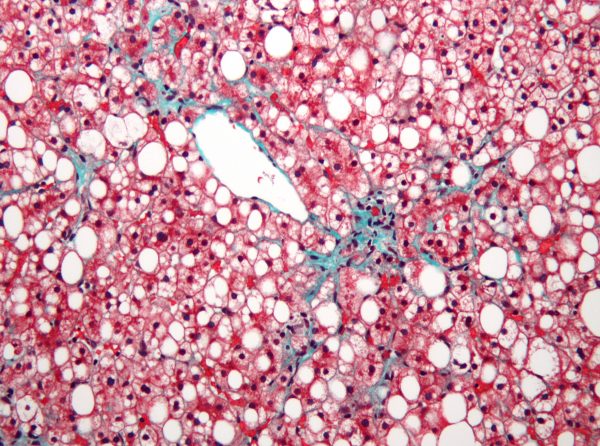

Non-alcoholic fatty liver disease — a disease in which the liver gets fat and cells start dying, eventually leading to organ failure — was a focus in this work, though the results also impact other diseases related to lipid metabolism like diabetes, obesity and metabolic syndrome.

“We don’t even know how many different triglycerides there are — hundreds, thousands,” says McDevitt. “We found that some triglycerides correlate positively with a fatty liver, while others correlate negatively with a fatty liver. Lumping all triglycerides into one class masks these subtler associations.”